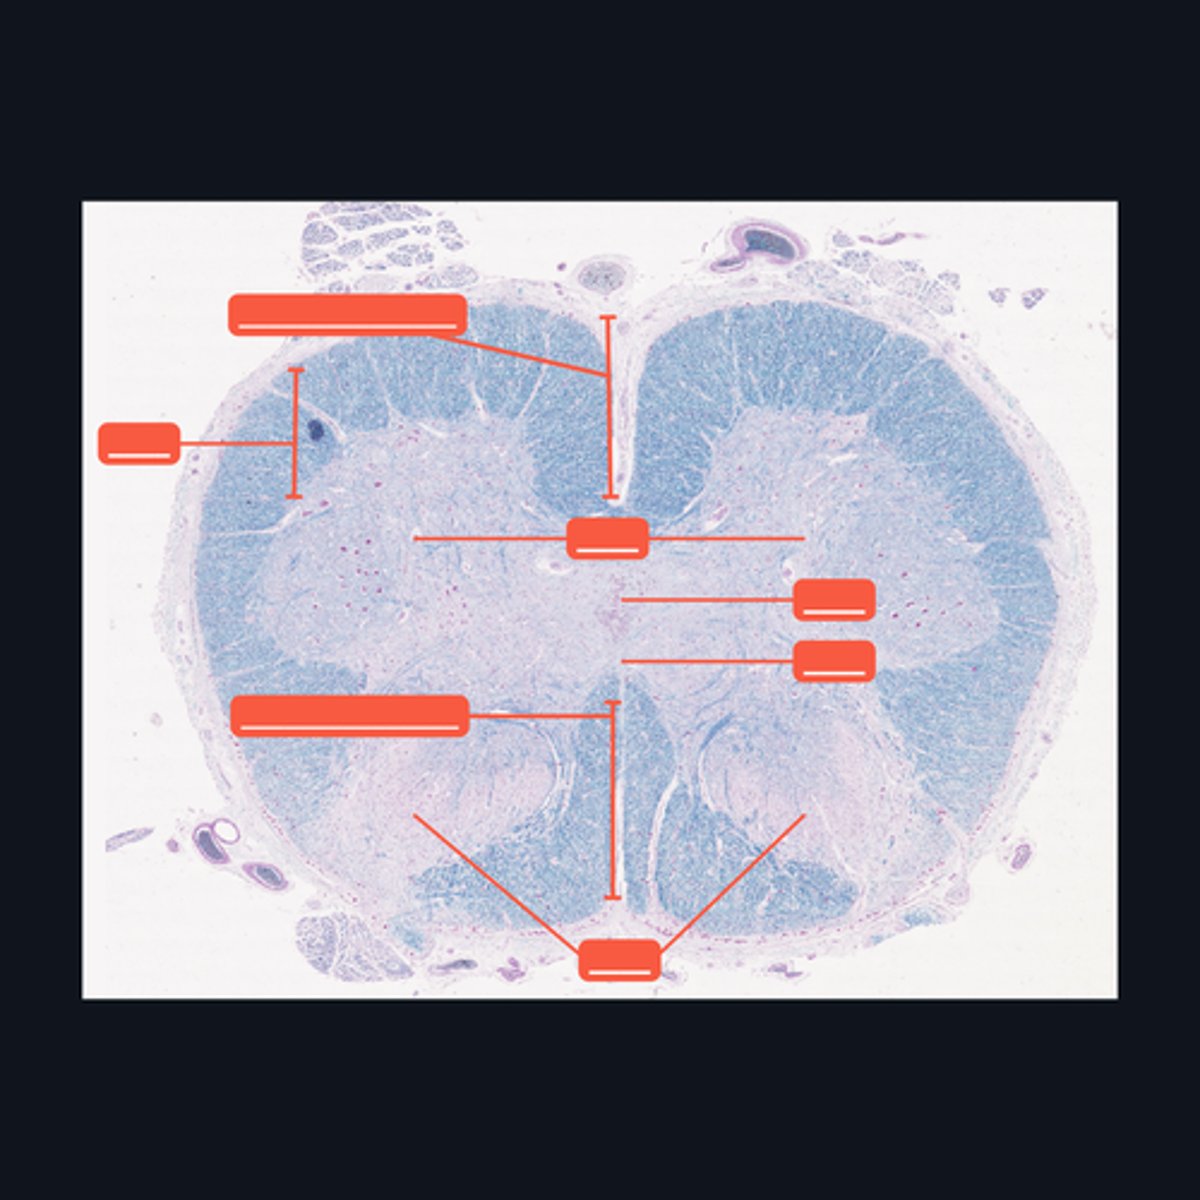

Identify the pointed region in the spinal cord

(1) Ventral Horn, (2) Dorsal Horn

Identify the pointed regions of the gray matter of the spinal cord

Identify the region of the spinal cord in the given image.

(top to bottom)

Ventral median fissure

White matter

Ventral horns

Central Canal

Central commissure

Dorsal midline sulcus

Dorsal horns

Identify the parts of the sacral region of the spinal cord.